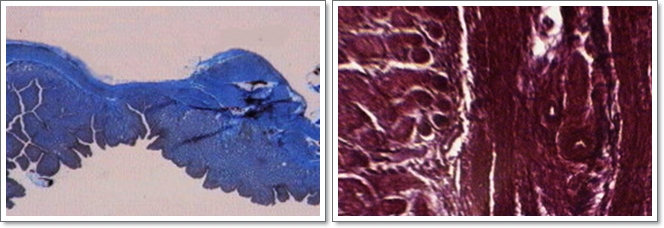

Trompa uterina És un conducte d'una llargària de diversos centímetres, que té la missió de transportar els òvuls madurs fins a l' úter gràcies a nombrosos cilis mòbils que entapissen la paret interna. És interessant fer constar que la fecundació es produeix sempre dins les trompes, i no dins l'úter; l'òvul fecundat segueix el camí vers l'úter, i es fixa a l' endometri (la paret interna), originant l'òrgan de connexió amb la mare, que és la placenta. (abaix esquerra)

Testicle de porc Exemple representatiu de gònada masculina, perquè l'estructura dels testicles de tots els mamífers és similar i dissenyada a base de tres parts diferenciades: una coberta fibrosa i resistent, centenars o milers de conductes seminífers encarregats de la producció dels espermatozoides, que es troben en gran quantitat i envoltats, i l'estroma, que és un teixitconjuntiu lax molt vascularitzat. Les cèlúlules intersticials tenen funció endocrina i produeixen l'hormona masculina anomenada testosterona (Dalt dreta)

Epidídim de porc És el conducte encarregat de completar la maduració dels espermatozoides, que avancen lentament a mida que experimenten el procés. Té, igual que el testicle -al qual està aferrat-, una coberta fibrosa, i acaba al principi del conducte deferent, que duu els espermatozoides fins a les vesícules seminals, per constituir la base de l' ejaculació Com a dada curiosa podem dir que el volum del líquid de l'ejaculació de l'home i del toro és normalment de 3-3,5 cc, mentre que en el porc és de 250 cc (Baix esquerra)

Ovari d'ovella És el lloc de formació dels òvuls, és a dir, la gònada femenina, i està constitu‹t per dues zones diferenciades: la zona medulúlar, molt rica en vasos sanguinis, i la zona cortical, on es poden apreciar gran quantitat de folúlicles de Graaf, que són els llocs on es desenvolupen els òvuls. (Dalt dreta).